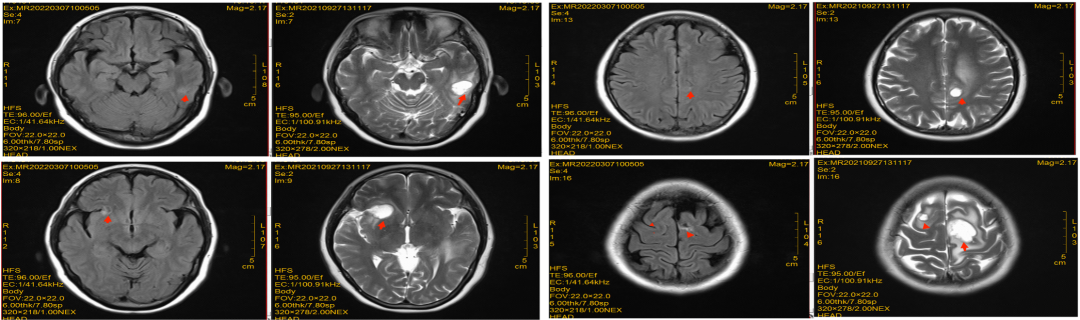

导言 在前两季的病例说栏目中,美宝整理了20例阿美替尼一、二线治疗的经典病例,并邀请相应的研究中心PI进行诊疗点评,以期为临床用药提供指导。本季度病例说仍初心不改,继续对临床中的真实病例进行深层次、多方面地解析,帮助更多临床医生全面了解阿美替尼,为更多患者带来更优治疗方案。 高波 深圳市第二人民医院呼吸内科 副主任医师 中国中药协会呼吸病药物研究专业委员会青年委员会委员 广东省医师协会呼吸科医师分会第四届委员会感染与重症专业组成员 广东省胸部疾病学会弥漫性实质性肺疾病多学科诊疗专业委员会委员 广东省医疗行业协会呼吸病管理协会常委 广东省预防医学会呼吸病预防与控制专业委员会第一届委员会青年委员会委员 深圳市抗癌协会肺结节专业委员会常委 深圳市抗癌协会胸部肿瘤MDT委员会常务委员 深圳市医师协会呼吸内科医师分会第二届理事会肺癌学组委员 深圳市中西医结合学会呼吸病专业委员会委员 深圳市医学会第一届睡眠医学专业委员会青年委员 深圳市健康管理协会第一届呼吸专业委员会委员 病史介绍 辅助检查 图2:颅脑MRI检查 2021.09全身骨扫描:左侧股骨上段骨盐代谢异常活跃,左侧坐骨骨盐代谢稍活跃,考虑恶性肿瘤骨转移可能性大。 2021.09 病理补充诊断:刷检见异型上皮细胞,考虑腺癌。左上叶舌段,活检符合肺浸润性腺癌。 图3:病理检查 病理诊断 病例简介

脑转移病灶:一线阿美替尼联合化疗治疗颅内病灶,第二次疗效评估即治疗5个月(20220308)后疗效评价为PR,治疗12个月后(20221011)患者脑转移病灶疗效仍为PR。

图5:治疗5个月颅脑MRI检查

图6:治疗约12个月颅脑MRI检查